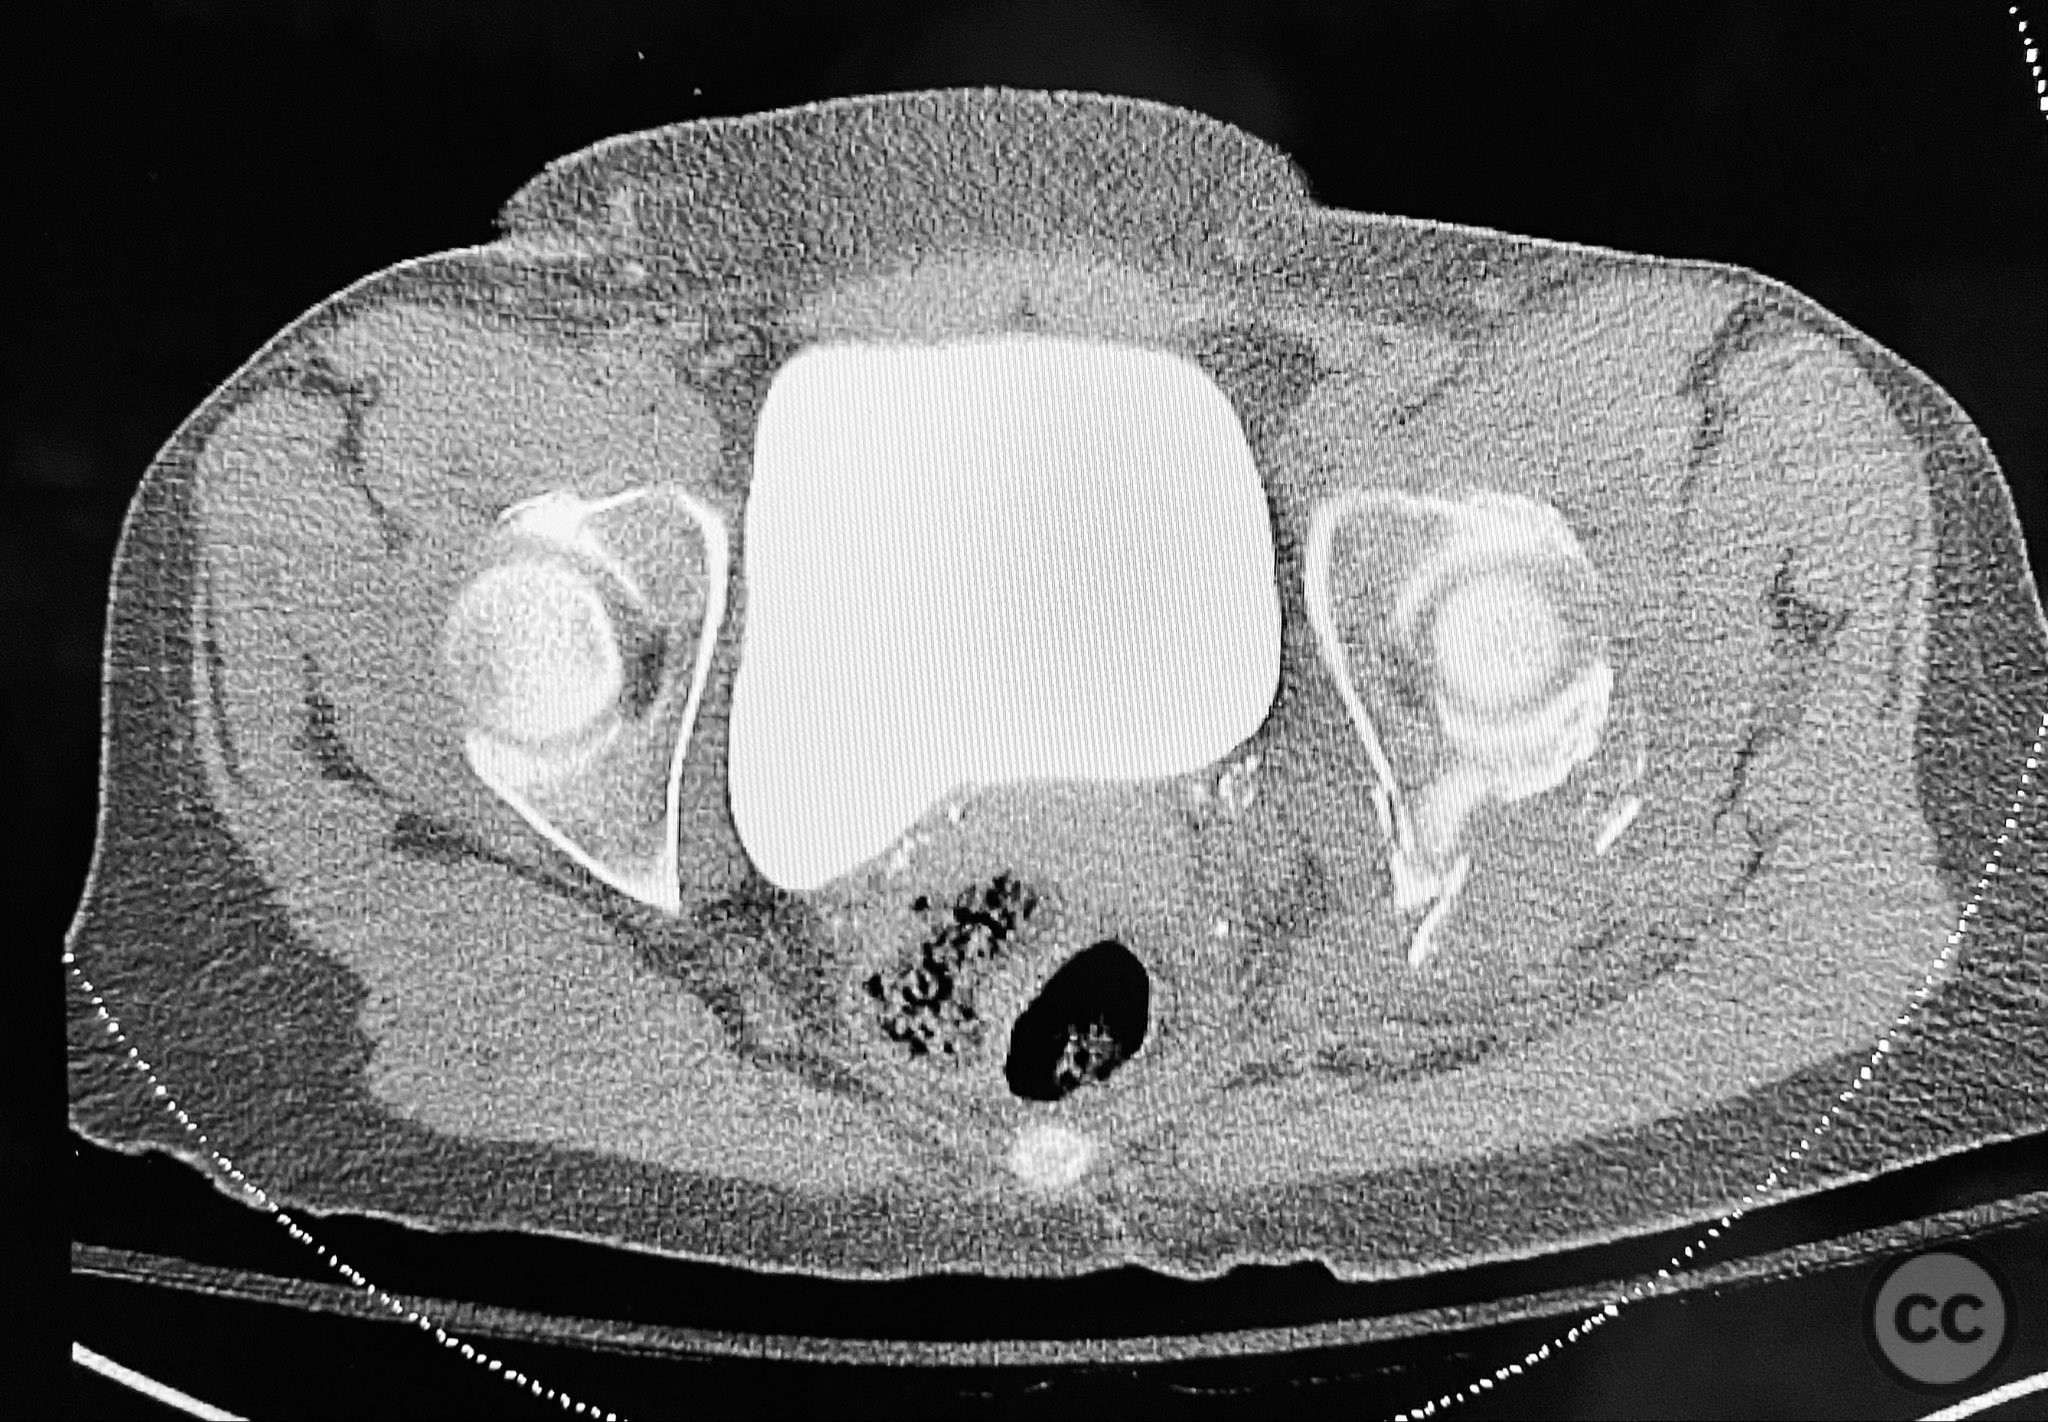

Clinical and radiological findings:  A patient sustained a posterior wall acetabular fracture-dislocation, characterized by comminution of the posterior wall, impaction of fragments into the posterior column region, and intra-articular loose fragments within the fossa acetabuli. Sagittal imaging demonstrated femoral head impalement on the intact wall, raising concern for potential irreducibility. Coronal and axial CT images revealed acetabular and femoral head impactions, peripheral wall comminution, incomplete fracture extension at the acetabular notch and quadrilateral surface, and an articular fragment within the joint. Surface renderings confirmed the extent of peripheral wall comminution and impaction. Despite these findings, a closed manipulative reduction was successfully achieved, resulting in a congruent reduction on post-reduction imaging.